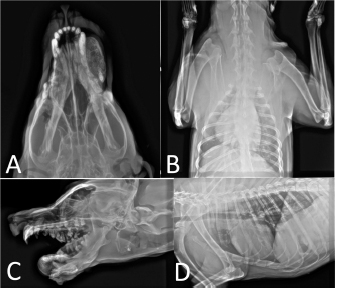

Fig. 2. (A and C) Thoracic radiographs which are depicted there was no metastasis to the lungs. (B and D) The radiographs from the mandibular mass was performed.

AbstractBackground: Osteoma is a benign bone tumor that rarely affects animals. The most common bones involved with this tumor included the mandible, maxillofacial bones, and nasal sinuses. Definitive diagnosis is based on pathology findings which allow for differentiation with other bone lesions. Case Description: The patient, a 5-year-old intact male Mongrel dog presented with a huge mandibular mass that involved both the right and left mandible, and led to dental occlusion. The radiography was performed and depicted the intense mass with a well-demarcated edge, a short transitional zone between normal and abnormal bone, and a smooth rounded radiopaque appearance. The investigation according to the fine needle aspiration showed the presence of oval to spindle shape cells with poorly malignancy criteria, fatty cells, reactive osteoblasts, and osteoclasts based on a population of spindle-shaped cells, and low numbers of degenerated neutrophils, bacteria, and few macrophages. Then, the radiographic assessments and cytology findings demonstrated the osteoma and were referred for surgical intervention. A unilateral mandibulectomy was performed, and the lesion was sent to the histopathology laboratory. The histopathology evaluation showed osteocyte proliferation without malignancy features. The osteoblast cells also showed no atypical proliferation that endorses the osteoma tumor. Conclusion: Although mandibular and maxillofacial bone resection in small animals have different tolerations, this patient became a candidate for surgery for future better nutrition and prevention of facial deformity and dental malocclusion. Follow-up after osteoma is one of the most necessary post-operation treatments to check the regeneration of the mass. There are considerable data in this report that should regard this tumor as a possible differential diagnosis for mandibular tumors. Keywords: Osteoma, Mandibulectomy, Bone, Dog, Histopathology. IntroductionOral neoplasms are the fourth most common neoplasia in dogs and, approximately seven percent of all tumors in this animal (Priester and McKay, 1980; Hoyt, 1984). Many factors contribute to the diagnosis of the masses as sex, breed, location, growth pattern, bone involvement, vessel invasion, lymph node invasion, metastasis, and recurrence (Simons, 2015). Osteoma is a benign tumor of bone (trabecular or dense lamellar) tissue (Van Duijl et al., 2018). They do not invade the cortical surface or undergo neoplastic changes. In humans, osteoma is specified as central, peripheral, and extra-skeletal (Kye et al., 2012). Osteoma is reported in the non-osteoid organs such as the stomach (Woo et al., 2019), skin (osteoma cutis) (Fernandez et al., 2012), and tongue (lingual osteoma) (Goldschmidt and Thrall, 1985). The most significant region of the osteoma tumor is the maxillofacial bones, such as the mandible, maxillae, and nasal/frontal bone, and maxillofacial bones are more susceptible to osteoma formation (Ogbureke et al., 2007; Sadeghi et al., 2015; Khandelwal et al., 2016). The purpose of this study is to describe the mandibular osteoma in a 5-year-old dog undergoing a surgical procedure to remove this tumor by mandibulectomy. Also, this report explains the treatment modality for this patient against an associated mandibular osteoma bone tumor treatment. Case DetailsThe 5-year-old vaccinated male intact mongrel breed was referred to Hassanzadeh Specialized Pet-hospital with a huge mass on the mandibular bone. The owner declared the mass appeared over 5 months. The clinical presentation started with drooling, problems in chewing, opened mouth caused by mass distention, malocclusion in the right mandible, and face changes. The right mandibular canine and first premolar tooth were not observed, the second premolar tooth was dislocated and the maxillary canine on the same side was oriented rostrally. There were no signs of pain and the mass was firm and bony consistency. Also, there was a smaller mass on the right mandible with lower invasion and lack of changes in dental occlusion (Fig. 1). The differential diagnosis of the mentioned case predicts old malunion fractures, and bone tumors such as osteosarcoma, osteoma, osteoblastoma, ossifying fibroma, and osteomyelitis or exostoses. Other jaw soft tissue masses such as epulis, squamous cell carcinoma, and ameloblastoma have rejected the cause of the consistency and bone structure of the mass. Diagnostic imagingThe skull radiographs were performed in dorsoventral and lateral projection which showed the intense and well-demarcated edge with a short transitional zone between normal and abnormal bone. There was a smooth rounded radiopaque appearance rostral of bilateral mandibles. The right mass size measured 8 × 4 cm and prevent normal chewing. The left mass has no remarkable changes in radiology in comparison to the left mass. The periosteal reaction and invasion of the surrounding soft tissue were not seen. Thoracic radiographs did not indicate pulmonary metastasis (Fig. 2).